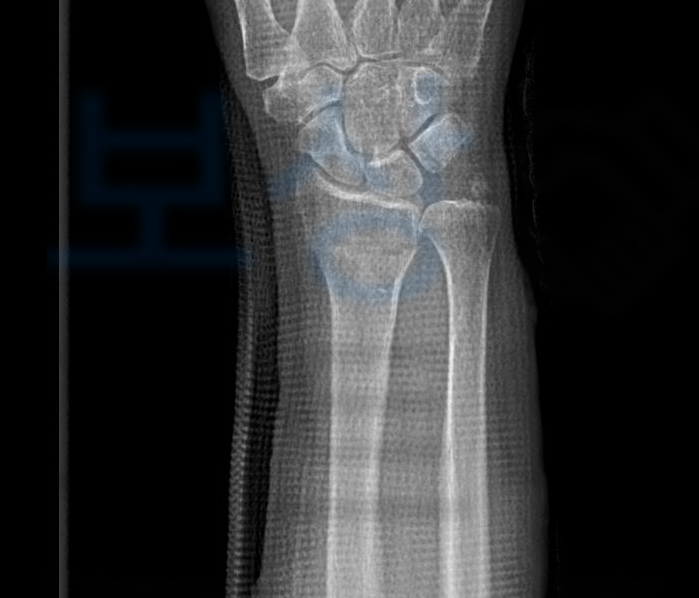

실제 저희가 진행해드렸던 김@@님은 버스요금을 내신 뒤에 의자를 향해 가시다가 버스가 급정거를 하는 바람에 뒤로 넘어지며 손목을 다치는 사고를 당하셨는데요, 이처럼 내 실수인지/ 버스의 잘못인지 과실 산정이 애매한 상황에서!